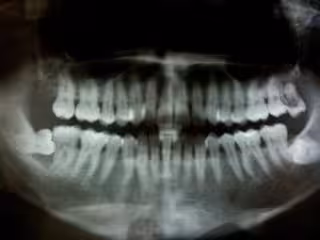

Periodontitis - FLICKR/FELIX E. GUERRERO - Archivo

"La enfermedad de las encías es una infección bacteriana crónica que afecta a las estructuras blandas y duras que sostienen los dientes y se asocia con la inflamación. Debido a que la inflamación parece desempeñar un papel importante en el desarrollo y el empeoramiento de la aterosclerosis, o 'endurecimiento' de los vasos sanguíneos, investigamos si la enfermedad de las encías está asociada con bloqueos en los vasos cerebrales y accidentes cerebrovasculares causados por la aterosclerosis de los vasos cerebrales", explica el autor de los estudios, Souvik Sen, del Departamento de Neurología de la Escuela de Medicina de la Universidad de Carolina del Sur (Estados Unidos).